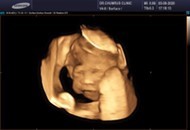

หมอบอกหนูเป็นผู้หญิงจ้า #ซาว21w